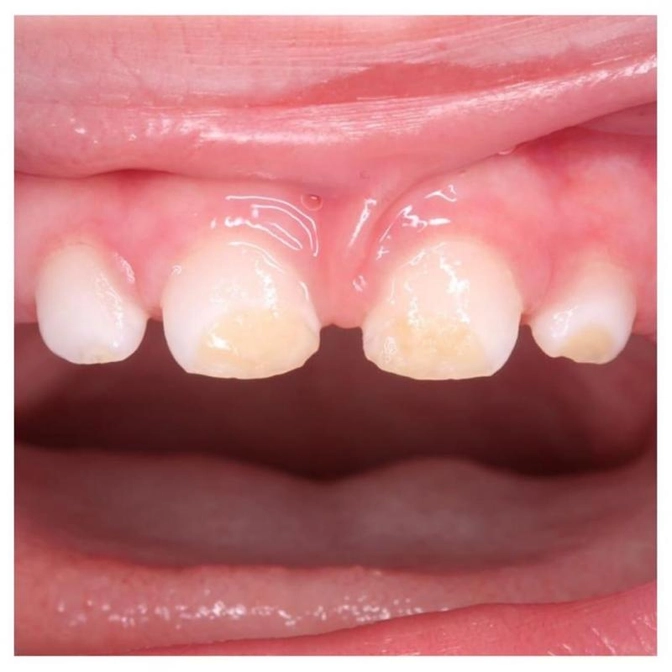

Пациент совсем еще малыш - 1,3 года.

На его зубках гипоплазия, уже осложненная кариесом, к сожалению.

Мальчик не давал маме тщательно рассмотреть зубки и она даже не заметила, что они прорезались уже измененные.

• Изменением цвета зуба.

• Пятна округлой формы белого, реже желтоватого, цвета, с четкими границами и блестящей, гладкой поверхностью (реже - тусклой).

• Изменением структуры - более тяжелая форма, которая проявляется углублениями в эмали там, где их быть не должно.

• Полным отсутствием эмали.